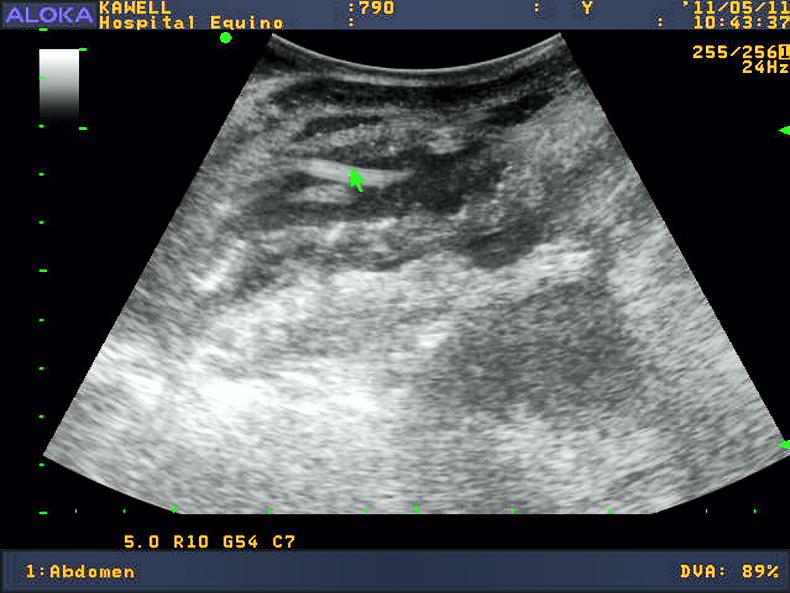

Larval stages cannot be diagnosed definitively and therefore disease based on larval migration is largely diagnosed based on clinical signs and response to therapy. Luminal stages can be detected by ultrasonography.